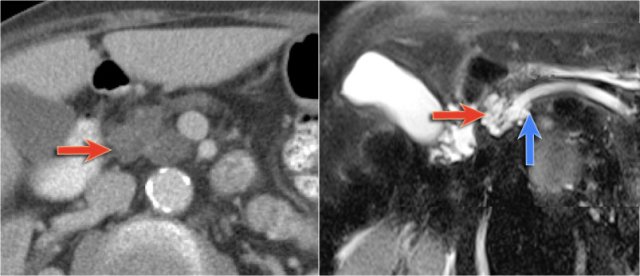

Another example of a serous cystic neoplasm (Fig).

The contrast-enhanced image on the right shows a hypodense lesion with central calcification in the body of the pancreas and subtle enhancement of septations

Notice that on CT it is very difficult to appreciate the cystic nature of these lesions and you might think that you are dealing with a pancreatic adenocarcinoma.

MRI will easily demonstrate the cystic nature of these lesions (fig).

The T2WI with fatsat nicely demonstrates a lobulated hyperintense lesion with central scar, which is characteristic of a SCN.